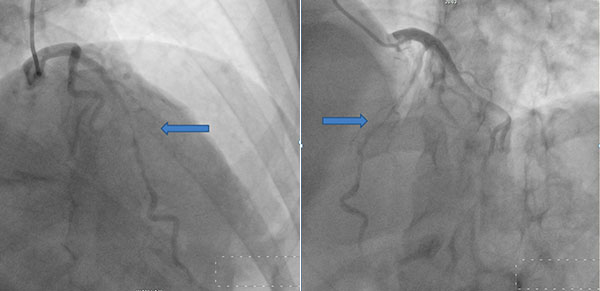

44岁的阿不拉,因反复胸痛半年余入院。经过冠脉造影、冠脉CTA检查确诊前降支心肌桥。此前经过了3个月左右的系统药物治疗,但是心绞痛症状仍然频繁发作。从冠脉造影图像可以清晰看到:冠状动脉最重要的分支——前降支中上段明显受压、狭窄成一线状,几乎没有血流通过。经过仔细评估,手术组制定了下一步治疗方案:必须外科手术矫治,首选心肌桥松解术,即切开覆盖、压迫前降支的心肌。

冠脉造影:前降支中上段明显受压、狭窄成一线状,几乎没有血流通过